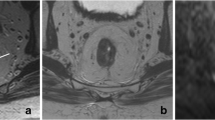

Example of patient with a CR where T2W-MRI (a) revealed marked hypointense residual wall thickening resulting with an equivocal (confidence level 2) score. Clinical assessment (b) revealed a white scar with some stenosis and distortion, and small superficial ulceration, also resulting in an equivocal score. DWI (c) revealed absence of diffusion restriction indicating CR